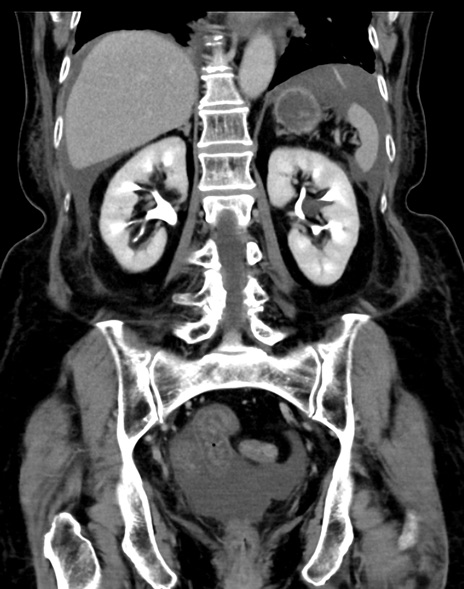

症例13 CT(冠状断像)1日半後